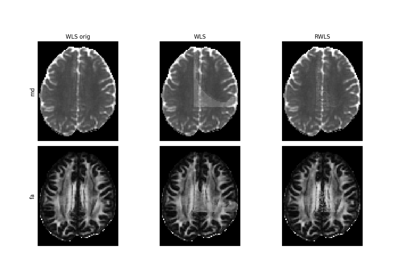

Patch2Self: Self-Supervised Denoising via Statistical Independence

Denoise images using Local PCA via empirical thresholds

Denoise images using Adaptive Soft Coefficient Matching (ASCM)

Denoise images using the Marcenko-Pastur PCA algorithm